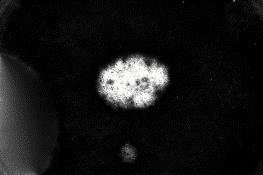

Skin lesion segmentation is one of the crucial steps for an efficient non-invasive computer-aided early diagnosis of melanoma. This paper investigates how color information, besides saliency, can be used to determine the pigmented lesion region automatically. Unlike most existing segmentation methods using only the saliency in order to discriminate against the skin lesion from the surrounding regions, we propose a novel method employing a binarization process coupled with new perceptual criteria, inspired by the human visual perception, related to the properties of saliency and color of the input image data distribution. As a means of refining the accuracy of the proposed method, the segmentation step is preceded by a pre-processing aimed at reducing the computation burden, removing artifacts, and improving contrast. We have assessed the method on two public databases, including 1497 dermoscopic images. We have also compared its performance with classical and recent saliency-based methods designed explicitly for dermoscopic images. The qualitative and quantitative evaluation indicates that the proposed method is promising since it produces an accurate skin lesion segmentation and performs satisfactorily compared to other existing saliency-based segmentation methods.